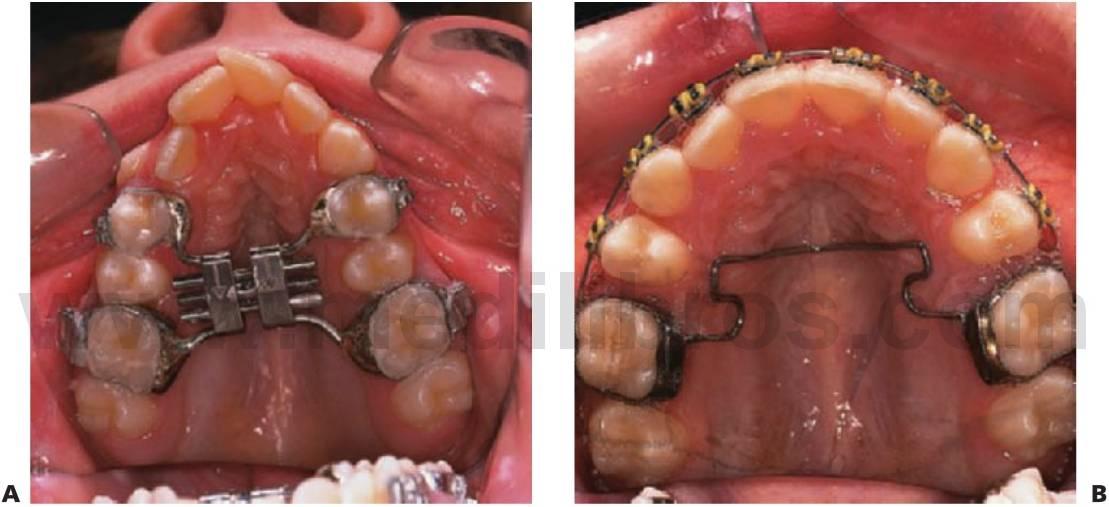

Expansión maxilar lenta: quad hélix/expansores de níquel-titanio

El quad hélix se ajusta a las bandas molares que se cementan en los primeros molares permanentes.

El dentista controla la activación del aparato.

La reactivación se realiza en visitas alternas y se puede realizar de forma intraoral mediante el uso de un alicate de tres puntas o extrayendo el aparato de la boca y realizando la expansión a mano.

La expansión debería proseguir hasta sobrecorregir los molares y se mantendría el aparato de esa forma durante 3 meses más. Así, la mordida cruzada suele corregirse en 4-6 meses.

El quad hélix puede utilizarse al mismo tiempo que la aparatología fija.

Los expansores de níquel-titanio precisan menos ajuste que los quad hélix convencionales de acero inoxidable.

Producen una cantidad predeterminada de expansión.

El enfriamiento del expansor permite constreñirlo e insertarlo en los tubos linguales de los molares superiores.

Cuando se calienta a la temperatura corporal, se convierte en elástico y ejerce una fuerza continua en los dientes que provoca la expansión de arco.

Las fuerzas de expansión producen también la desrotación simultánea de los molares (figs. 11.14, 11.15).